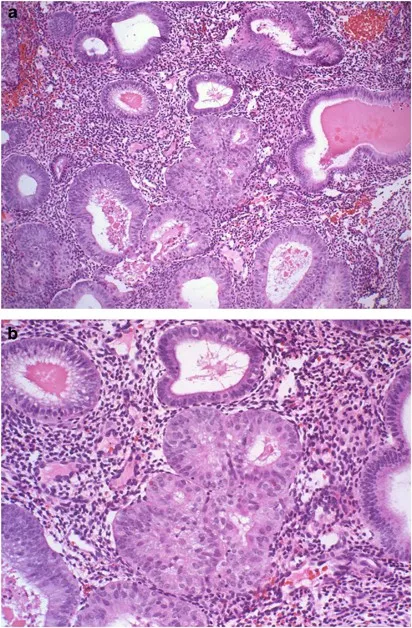

| Pathology | Proliferation of glands | Malignant glandular proliferation |

- Derived from coelomic epithelium; CA-125 marker.

- Serous: Often bilateral. Psammoma bodies common in malignant types.

- Granulosa Cell Tumor: ↑ Estrogen (endometrial hyperplasia). Call-Exner bodies (rosettes).